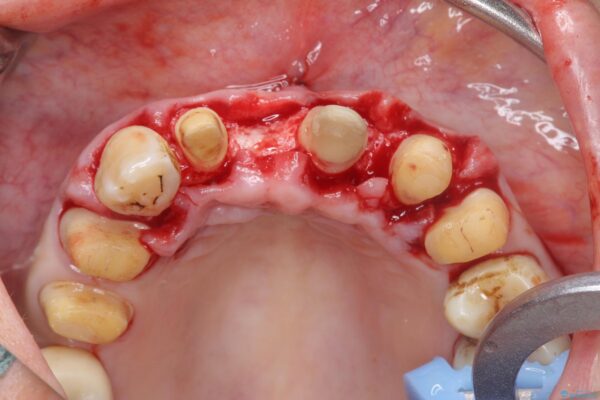

治療中

歯の総合的なマネージメントを行う包括的歯科治療の実践[ 歯周病・矯正・セラミック補綴 ] 治療中画像 歯の総合的なマネージメントを行う包括的歯科治療の実践[ 歯周病・矯正・セラミック補綴 ] 治療中画像 歯の総合的なマネージメントを行う包括的歯科治療の実践[ 歯周病・矯正・セラミック補綴 ] 治療中画像 歯の総合的なマネージメントを行う包括的歯科治療の実践[ 歯周病・矯正・セラミック補綴 ] 治療中画像 歯の総合的なマネージメントを行う包括的歯科治療の実践[ 歯周病・矯正・セラミック補綴 ] 治療中画像 歯の総合的なマネージメントを行う包括的歯科治療の実践[ 歯周病・矯正・セラミック補綴 ] 治療中画像 歯の総合的なマネージメントを行う包括的歯科治療の実践[ 歯周病・矯正・セラミック補綴 ] 治療中画像 歯の総合的なマネージメントを行う包括的歯科治療の実践[ 歯周病・矯正・セラミック補綴 ] 治療中画像 歯の総合的なマネージメントを行う包括的歯科治療の実践[ 歯周病・矯正・セラミック補綴 ] 治療中画像 歯の総合的なマネージメントを行う包括的歯科治療の実践[ 歯周病・矯正・セラミック補綴 ] 治療中画像 歯の総合的なマネージメントを行う包括的歯科治療の実践[ 歯周病・矯正・セラミック補綴 ] 治療中画像